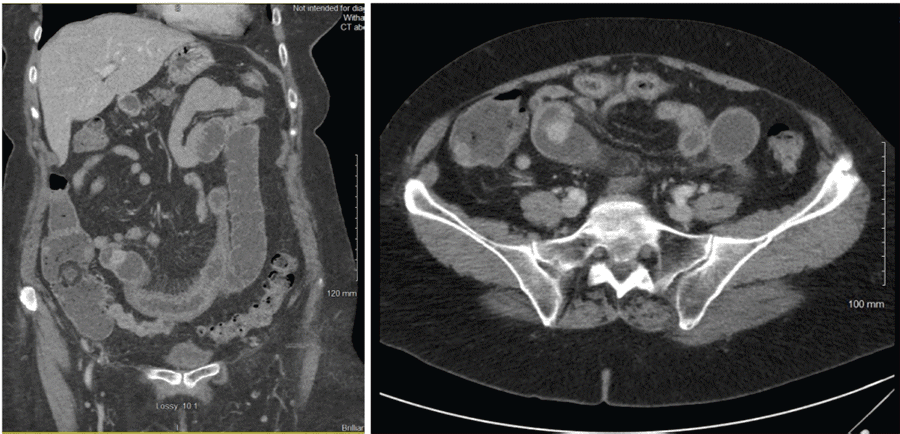

The patient's workup in the emergency department included a CBC, CMP, and lipase with no relevant findings. A CT scan of her abdomen and pelvis with intravenous contrast with 5 mm slides a small bowel mass in the right lower quadrant causing a small bowel obstruction (Figure 1). The patient improved after symptomatic treatment in the emergency department and was released with follow-up with a gastroenterologist. In the following weeks, she underwent a CT enterography that showed extensive diverticula and a 1.3 cm enhancing mass versus focal peristalsis in the jejunum. A subsequent colonoscopy in late January showed pancolonic diverticulosis and two small tubular adenomas but was otherwise unremarkable. She was recommended to follow up with a surgeon, given the location of the mass, presumably in the mid-small bowel and therefore out of reach for most endoscopic practices.

Figure 1. CT of Abdomen and Pelvis with IV Contrast Showing 1.2 cm Mass in Mid-Jejunum. Published with Permission

A) Coronal plane of abdominal CT scan showing jejunal mass causing a partial bowel obstruction; and B) CT abdomen/pelvis axial view showing jejunal mass